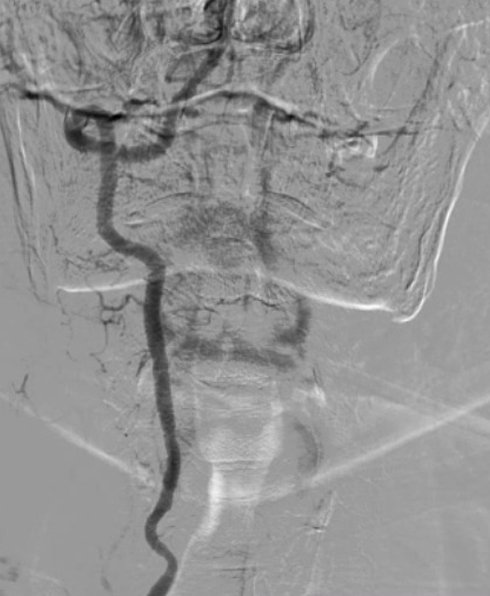

MRI/CT interpretation and Thrombectomy and stenting/ plasty for acute and recurrent stroke. Cerebral DSA

Thrombectomy – mechanical , pharmacological and combined therapy for acute stroke.

Portal hypertension , bleeding and Cirrhosis, Budd Chiari management.

Outcomes observed in patients treated with image-guided, minimally invasive vascular procedures.

Results vary by patient and condition. Images are for educational purposes only.